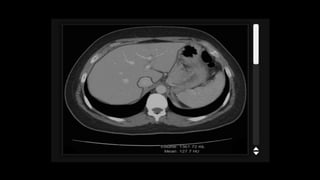

• On unenhancedCT normal liver parenchyma has homogeneous density, which can vary between 55 and 65 HU. • Exceeds that of the spleen by about 10HU. • Increased diffuse deposition of fat leads to reduction in attenuation • Increased glycogen – increased attenuation

• 68.

• Hepatic perfusioncycle can be differentiated into three phases. 1. Arterial phase 2. Redistribution or portal venous phase 3. Equilibrium or hepatic venous phase Bolus tracking is done and when aortic enhancement reaches a threshold of approximately 150HU, hepatic scanning is initiated.